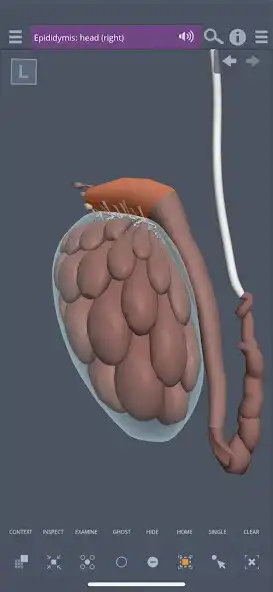

Primal's 3D Real-time Human Anatomy app for the Male Pelvis is the ultimate 3D interactive anatomy viewer for all medical educators, practitioners and students. Meticulously built over ten years from high-resolution cross-sectional photographs of real cadavers, the app provides an accurate and visually stunning reconstruction of the anatomy of the male pelvis.

The easy to use and intuitive interface lets you choose precisely the anatomy you want to see, from exactly the angle you want to see it. This flexibility is supported by a wealth of user-friendly tools to help you set up your ideal anatomical image, quickly and easily:

The Gallery contains 13 pre-set scenes, designed by an in-house team of anatomical experts, to clearly and comprehensibly present in-depth regional and systemic anatomy of the male pelvis. Each scene is divided into five layers to provide greater control over the depth of anatomy shown; making tailoring the anatomy you want to see simple and quick.

The Contents folders arrange all 405 structures systemically, meaning you can browse by subcategory and switch all related structures on at once. It provides an excellent learning tool for example turn on all branches of the internal iliac artery, or the muscles of the perineum.

The Contents layer controls split each system into five layers from deep to superficial. This allows you to quickly build up different systems to the depth you want to see.

Read detailed and accurate text for each structure using the T icon, and in a feature unique to Primal Pictures, each anatomical term in the text is linked to the appropriate model in the 3D model. Selecting these links will highlight the relevant structures, bringing the text to life and make learning anatomy more visual and immediate.

**Context**

See each structure in context with the anatomy that surrounds it. Explore these relationships and easily navigate to related anatomical structures to expand your learning. Select a field name in the right-hand menu to show the anatomical category and sub-category of the structure for added understanding and simple navigation.